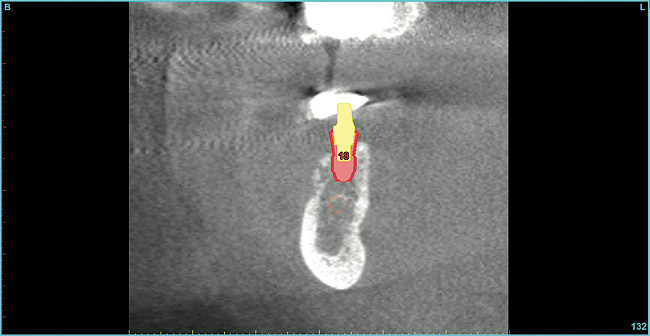

Figure 14  Cross-sectional cone-beam CT view of augmented extraction site No. 30.

Figure 14